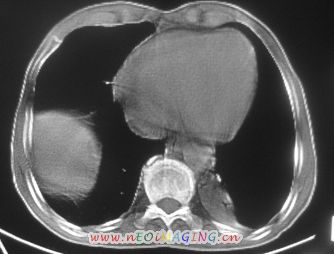

以下是引用卜一在2007-10-7 9:38:00的发言:[br]左下肺胸膜下团片影,内见含气支气管像,临近胸膜未见增厚。多考虑:1 左下肺炎症,建议消炎后复查!2 不除外肺隔离症合并感染!